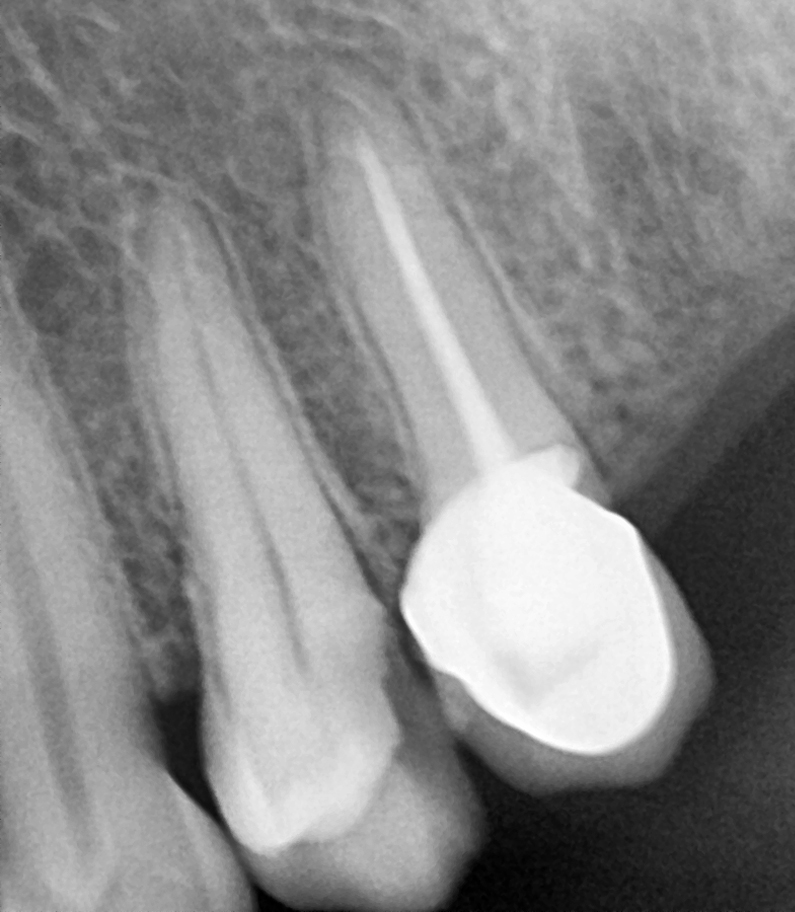

Is crown required?

Depending on the tooth, it is quite common to recommend placing a crown over the tooth within 3 months after root canal treatment, to provide maximum protection for the tooth in the long term.

The reason for this is because a tooth that has undergone nerve infection and pulp is removed thus tooth has become weak and brittle. A lot of biting forces fall on teeth when we eat and chew, so placing a crown on the tooth provides the tooth the necessary strength and durability.

Gallery